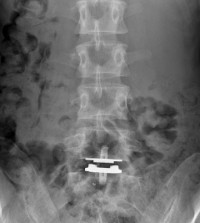

Prothese de face

Exemple de Prothèse discale :

prothèse L5-S1 vue de face